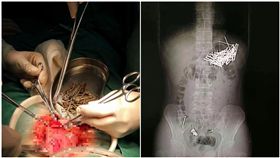

和女友吵架…他將87根鐵釘吞下肚

用來做裝潢的鐵釘竟然被當成食物吞下肚!湖南一名男子疑...